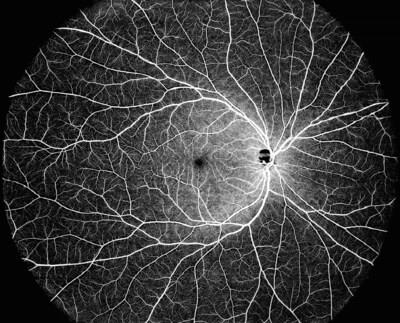

DREAM OCT is able to cover an ultrawide field single scan which delivers a 130° OCTA image. DREAM OCTTM swept-source 12 mm super-depth scanning allows superior imaging of the choroid and retina, and a large portion of the vitreous space. The super-depth anterior scanning capabilities achieves 16.2 mm (in air), allowing for the complete anterior segment from the cornea to the anterior part of the vitreous to be scanned in only one scan. The longer wavelength allows for superior penetration through opacities in either lens or vitreous.

Using ultra-wide swept-source technology, DREAM OCT was developed to address the needs of retina specialists, comprehensive ophthalmologists and their patients with highly-detailed imaging capabilities for improved care and results. Currently, more than 160 peer-reviewed papers have utilized findings from DREAM OCT devices.

Intalight Inc. was founded by a group of scientists and industry veterans of Silicon Valley with a core mission to develop the most advanced ophthalmic technologies. There are now three sites in Silicon Valley, Shanghai, and Luoyang. Intalight's Swept-Source Optical Coherence Tomography (OCT) device combines Deep imaging depth, Rapid sweeping speed, Extensive scan range, Accurate lesion detection and Multimodal imaging capabilities, and is abbreviated as DREAM OCTTM. The powerful imaging device has become an indispensable tool for many ophthalmologists in not only their daily clinical use but also their exploration of the research frontiers. To learn more about Intalight and DREAM OCT, please visit our website at and follow us on LinkedIn and Facebook .